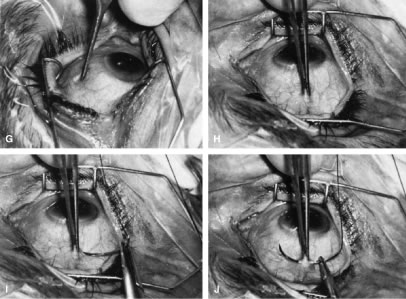

After the iridectomy is complete, the iris usually will return spontaneously into the anterior chamber unless it has suffered damage as a result of high pressure (as occurs in severe attacks of angle closure glaucoma). In patients with a reactive sphincter, it usually is necessary only to release the iris from the grasp of the incision. The iris can be stroked into position with the use of a blunt instrument on the corneal surface. Attempting to reposit the iris by directing a stream of irrigating solution into the incision is not recommended; the solution may enter the posterior chamber, forcing even more iris out of the incision. If the surgeon has difficulty restoring the iris to its proper position, injection through the previously placed paracentesis track of freshly mixed acetylcholine usually will solve the problem. In the eye with a dilated fixed pupil and a flaccid iris, it often is preferable to perform a sector iridectomy. Once the pupil is entirely round, the suture placed previously in the corneoscleral incision can be pulled up and secured promptly. Injecting balanced salt or acetylcholine solution through the previously placed paracentesis can deepen the chamber. In patients who have had recent angle-closure attacks and in whom peripheral anterior synechiae may be newly developed, forceful deepening of the anterior chamber at this point may tear open the synechiae and restore normal function of the anterior chamber. The procedure of chamber deepening must be done cautiously, with careful monitoring of IOP. A gonioprism, such as the Zeiss four-mirror lens, can be used with an operating microscope to monitor the effect on anterior chamber angle. At the close of the procedure, the pupil should be round, the chamber deep, and the incision sufficiently closed that there is no leakage. The IOP should be approximately 15 to 30 mm Hg, being raised to that level by injection through the keratostomy. Such a pressure may help prevent subsequent choroidal detachment and allows the integrity of the incision to be tested. If the corneoscleral incision has been properly placed and sutured, there should be minimal transient astigmatism. Vision should return to the preoperative level within several days. If the eye is inflamed, it usually is helpful to instill a short-acting cycloplegic agent such as cyclopentolate. Furthermore, the surgeon may give a subconjunctival injection of corticosteroid, although it rarely is necessary to do so. An antibiotic ointment and a light patch usually are applied until the facial nerve block has worn off. If there is a reasonable chance that the patient will need a filtration procedure at a later date, then the surgical procedure is modified to perform the iridectomy through clear cornea, rather than under a fornix-based flap. The technique is almost exactly the same, with the obvious exception that the incision is placed through clear cornea. Postoperative Care In almost all instances, iridectomy can be performed as an outpatient procedure. However, when associated with severe pain or when the attack of angle closure has been difficult to stop and has required extensive usage of carbonic anhydrase inhibitors and osmotic agents, admission of the patient to the hospital may be justified. Especially in older and infirm patients, the general state of health must be monitored carefully. It is important to verify that the patient has not become overly dehydrated or experienced an attack of congestive failure. The eye patch usually is removed from the treated eye as soon as the facial nerve block has worn off. If the procedure is done on an outpatient basis, a patch and shield may be left in place until the patient returns the next day for the first postoperative visit. A drop containing a corticosteroid can be used topically three or four times a day until the inflammatory response has disappeared, usually 4 to 7 days. Careful attention must be paid to the state of the pupil. The development of posterior synechiae is an important and usually unnecessary complication. Although it is not clear that posterior synechiae predispose the patient to the development of cataract, the presence of such adhesions makes extracapsular cataract extraction more difficult. Because many patients with angle-closure glaucoma will later have cataract extraction, the development of such adhesions may jeopardize the long-term visual result. Furthermore, inability of the pupil to dilate in the dark may limit the patient's visual function, especially in conjunction with a developing cataract. In most cases, dilating drops are used routinely until the inflammatory response has worn off. One acceptable program is to use tropicamide 1% at sufficient intervals to ensure that the pupil is dilated adequately for a period of approximately 1 week. The medication can be continued at bedtime for 2 to 3 weeks, or even longer, until it is certain that the inflammatory response has disappeared. Many patients are given pilocarpine preoperatively. There is a tendency to continue the administration of pilocarpine postoperatively, especially when control of IOP has been difficult. This practice should be discouraged. Pilocarpine will predispose patients to posterior synechiae and should be avoided if possible. The drug of choice for pressure control usually is topical epinephrine, a β-blocker, or epinephrine plus a β-blocker. If these two agents are not adequate, a carbonic anhydrase inhibitor can be used until the eye is entirely quiet, at which time pilocarpine can be reinstituted. In such cases, however, care should be taken to dilate the pupil periodically to prevent the development of posterior synechiae. Some surgeons may be reluctant to use dilating drops for fear of inducing angle closure. This possibility exists, but it is uncommon. Furthermore, it is preferable to know immediately whether the iridectomy has eliminated the possibility of angle closure caused by papillary dilatation. Therefore, this concern is an additional reason to use cycloplegic agents in the immediate postoperative period. Because of the possibility of an increase in IOP after dilatation, however, IOP should be checked carefully after the use of the cycloplegic agent. In addition, IOP should be monitored carefully during the initial postoperative period. Pressure spikes are not uncommon. These spikes are of little concern if the optic nerve is healthy. However, in patients with advanced glaucomatous nerve damage, such pressure spikes can be devastating; they should be avoided if possible. Postoperative evaluations ordinarily are made on the first postoperative day, after 1 week, and after 1 month. If a problem with the control of IOP is suspected, visual fields and disc photographs should be obtained. Complications The most serious complication after iridectomy is malignant glaucoma (aqueous misdirection, ciliary block glaucoma). Eyes predisposed to this complication are those with small anterior segments, typically seen in patients with marked hyperopia or small globes. Furthermore, there is some indication that eyes with high IOP preoperatively may be predisposed as well. Patients who have had an attack of malignant glaucoma in one eye are likely to have the same complication in the second eye. GUARDED FILTRATION PROCEDURES (TRABECULECTOMY) What traditionally has been called a trabeculectomy has become the standard filtration type of surgery for most cases of open-angle glaucoma. The name is a generic one, describing a wide variety of surgical methods, some substantively different from others.46–50 A goal of the original procedure was to allow filtration out of the cut ends of Schlemm's canal. In most cases, this mechanism does not appear to be the actual reason for the decrease in IOP that usually follows. Another theoretic explanation for its pressure-lowering effect, direct access of aqueous humor to the collector channels, bypassing diseased trabecular meshwork or Schlemm's canal, may be the actual mechanism for pressure reduction in a few cases. Exploration of the operative site does not disclose any area of gross filtration in some patients who have effective pressure lowering after surgery. It is likely that in such cases, aqueous humor exits into the collector channels or perhaps through the thinned scleral tissue. In most cases, the mechanism responsible for lowering IOP after guarded filtration procedure is a through-and-through fistula connecting the anterior chamber with the subconjunctival space. As such, the word trabeculectomy is a misnomer. Complete success is possible without removing trabecular tissue. Lamellar sclerokeratectomy would be a more accurately descriptive title, and it has been suggested in the past. However, the term is cumbersome and to some extent, inaccurate, because sclera is not always removed. Because the term trabeculectomy is a significant misnomer, we rarely use it in this chapter. The procedure performed currently functions as a filtration procedure; consequently, it is appropriately called a filtration procedure. When it is performed so that the filtering area is at least partially protected in an attempt to control the amount of filtration, the term guarded filtration procedure is appropriate and is used in this chapter. Consideration of how the operation actually works is not of purely academic interest; it materially affects how the surgery is performed and influences the final result. Patients with gross fistulas with filtering blebs resembling those seen with operations that were popular in the past, such as the corneoscleral trephine, usually achieve lower IOP than patients in whom the filtering bleb is thicker, more posterior, and less cystic. Furthermore, the thinner, polycystic bleb probably lasts longer, providing more years of low IOP. Consequently, if the surgeon wants to obtain IOP that is as low as possible, the guarded filtration procedure should be designed to produce gross filtration. Such a goal has its costs, however. A general principle of glaucoma surgery is that every millimeter of pressure-lowering effect has a price. This principle applies to guarded filtration procedure; the complication rate with procedures designed to produce gross filtration and lower IOP is greater than that with procedures that are more completely guarded and in which a higher final IOP is considered satisfactory, as discussed in detail in the first section of this chapter. The surgeon must carefully consider the major goal of the surgery being planned. For example, for the patient who has uncontrollable angle-closure glaucoma and is predisposed to flat chamber or even malignant glaucoma, the surgeon probably will fashion the scleral flap and suture it in place so that leakage is minimal. On the other hand, for a patient with high myopia with glaucoma that is progressive at a pressure level of 14 mm Hg, the surgeon probably will want to make the flap thin or ensure that there is leakage around the edge of the flap, or both, to have the greatest likelihood of gross filtration with a low final IOP. Factors predisposing patients to the final level of IOP are shown in Tables 14, 17, and 18. As shown in these tables, the more the surgical procedure mimics the classic Elliot corneoscleral trephine, the more reasonable to expect a final low IOP. Also, there is more likelihood of flat anterior chamber, choroidal detachment, cataract development, and a thin cystic bleb predisposing to endophthalmitis. Several modifications have been suggested for achieving a low final IOP with a reduced incidence of side effects. These include the placement of sutures so that they can be released easily in the postoperative period27,51–53 and the transconjunctival cutting of sutures postoperatively with a laser.54–57 These techniques are discussed later in this chapter. In routine cases, we prefer a limbus-based flap (Fig. 13). The development of this type of flap is only slightly more difficult than fashioning a fornix-based flap (see Fig. 11), but its advantages are significant. Compared with procedures performed with a fornix-based flap, the limbus-based operation is more likely to eliminate problems with postoperative leakage through the conjunctiva. In contrast, leakage at the cut edge of the conjunctiva of a fornix-based flap is common in the immediate postoperative period. Furthermore, cooperation under the limbus-based flap tends to be easier than with the procedure performed with the fornix-based flap. In addition, and of great importance, localized deformation of the wound in the immediate postoperative period for the purpose of encouraging filtration is performed more easily and safely when the radial grooves are covered with a limbus-based rather than a fornix-based flap. Because we often use this procedure [the Carlo Traverso maneuver (CTM)],58 the security afforded by the limbus-based flap is welcome. Thus, in most cases, the limbus-based flap is preferred. An exception is the case in which previous filtration surgery has failed and in which development of a limbus-based flap appears unjustifiably difficult and risky. Preoperative Care A careful history should be taken to determine whether systemic medical issues may affect the operative or postoperative course. For example, breathing problems and spinal arthritis may prevent the patient from lying completely flat. Chronic coughing or constipation with straining may increase the risk of postoperative suprachoroidal hemorrhage. Other relevant information includes what allergies are present and if the patient has a proclivity to excessive bleeding. Bleeding studies, such as prothrombin time, platelet count, and, in some cases, bleeding time, are appropriate in certain cases. Patients who are taking aspirin should not do so at least a week preoperatively, if possible. Similarly, anticoagulants should be discontinued long enough preoperatively to allow the coagulation characteristics to return to satisfactory levels. The eye should be as quiet as possible. Long-acting miotics, such as echothiophate, should be discontinued at least 3 weeks before surgery. If possible, pilocarpine or other short-acting miotics also should be discontinued long enough before surgery to allow their effect to wear off. Any signs of medication allergy may warrant discontinuation of the offending agent and sometimes preoperative topical steroids to quiet the inflammation, reducing intraoperative bleeding and postoperative scarring. The purpose of the surgery must be clear to the patient and the surgeon (see Table 1). Full discussion of the reasons for considering the surgery is essential, including alternative therapies and complications. Patients must understand that the usual goal of surgery is not improved visual acuity; visual acuity probably will be different and may be worse after the operation. Postoperative care must be discussed before surgery, with patients having a clear understanding of the need for continuing, careful monitoring of their condition. If it will be difficult for the patient to return to the operating surgeon, other arrangements that are satisfactory to both patient and surgeon must be made before the operation. Before the patient is sedated or anesthetized, the surgeon should again ensure that the patient's expectations and anticipations are realistic. Anesthesia Depending on the patient, surgeon, and procedure, anesthesia may range from general endotracheal anesthesia to topical agents alone. General anesthesia is reserved for patients unable to cooperate and hold still for the duration of the procedure. Retrobulbar or peribulbar injection of short- and medium-acting anesthetics, such as lidocaine and mepivacaine, with or without hyaluronidase are usually adequate. Some surgeons do not include hyaluronidase in the retrobulbar block because it may make the subconjunctival tissues boggy, complicating the surgery and making evaluation of the postoperative bleb more difficult. A facial block, such as a modified O'Brien facial nerve block,45 with approximately 10 ml of a short-acting agent, such as lidocaine or mepivacaine, may reduce lid squeezing. Most patients have only light sedation, such as 4 to 6 mg intravenous diazepam (Valium). In many cases, no sedation is necessary. Surgeons anticipating shorter, routine cases with cooperative patients may be comfortable with topical anesthesia, such as lidocaine jelly and topical tetracaine. If an iridectomy is planned, topical anesthesia may be supplemented with intracameral (nonpreserved) lidocaine 1%. Intracameral lidocaine may result in dilation of pupil, necessitating intracameral miotics before the iridectomy to prevent accidentally large iridectomies. We prefer to perform guarded filtration procedures with a modified O'Brien facial nerve blocky with approximately 10 ml of a short-acting agent, such as lidocaine or mepivacaine, in addition to a retrobulbar block with the same agent. Hyaluronidase is not included in the retrobulbar block because it tends to make the subconjunctival tissues boggy, complicating the surgery and making evaluation of the postoperative bleb more difficult. Most patients have only light sedation, such as 4 to 6 mg intravenous diazepam. In many cases, no sedation is necessary. Many patients are older, and in some, the only eye with useful vision is having surgery; therefore, the sooner the patient can be completely ambulatory after surgery, the better. In addition, in most cases, the goal of surgery is to develop a functional fistula, so it probably is helpful to remove the patch as soon as possible after surgery to encourage blinking and automassage. In some instances, especially with topical anesthesia, it is not necessary to apply a patch at all. In addition, rapid ambulation helps to ensure that the patient maintains a posture that prevents blood from settling in the area of the procedure. The use of short-acting agents and minimal sedation encourages prompt return to full normal function, an important consideration in the older person with sensory deprivation. Operative Technique The limbus-based conjunctival flap should be developed as far superiorly in the superior fornix as possible (Figs. 13 and 14). The conjunctival incision should be sufficiently far posteriorly that it involves the thick tissue overlying the superior rectus muscle; if it is made more anteriorly, the likelihood of leakage through the incision increases. This leakage is especially a problem when agents specifically used to combat postsurgical scarring are employed. Toothed forceps, or even serrated forceps with indentations that are sharp enough to cut the conjunctiva, should not be employed. On the other hand, a common error is to forget the normal elasticity of the conjunctiva and consequently to neglect to stretch the tissue sufficiently to permit clear identification of the edges of the incisions. This problem is a special concern with Tenon's capsule, which tends to retract out of the operative field, and may be overlooked unless specific attention is paid to bringing it into view. To facilitate a posterior incision, a superior rectus bridle suture may be placed and gently affixed to the drape. A second alternative is the corneal traction suture. A 7-0 Vicryl suture is placed through the peripheral cornea, approximately 0.5 to 1.0 mm from the limbus. The suture should be placed at least ½, but not full thickness, with plane of the spatulated needle parallel to the surface of the cornea in midbite, so that the cutting sides of the suture do not create tracks that may facilitate cheesewiring through the cornea. The eye is then rotated inferiorly, the suture entry and exit from the cornea checked for leakage indicative of an inadvertent full thickness passage, and the suture affixed to the drape with two pieces of tape, folding the suture of the first to prevent slippage. Sterile adhesive medication labels work well. The incision in the conjunctiva and Tenon's capsule should be long enough to permit easy retraction of the tissue toward the limbus, providing good visibility. A 10-mm incision is average. It is better to have the incision longer than shorter. If the initial incision is made directly over the insertion of the superior rectus muscle, it should not be carried deep into the tissue, because the muscle could be cut. Rather, the edge of Tenon's capsule and conjunctival tissue should be held firmly, and the underlying tissue separated with blunt dissection. The scissors should be tilted anteriorly toward the limbus to avoid the underlying muscle and the rich vascular network surrounding it. The blunt dissection is continued until Tenon's capsule is completely incised. A second approach is to make the incision in the supertemporal or supernasal quadrant, 8 mm or more posterior to the limbus, through conjunctiva and Tenon's capsule down to bare sclera. This approach avoids the risk of immediate damage to the muscle with bleeding. The scissors are then used bluntly spread and dissect the plane between Tenon's capsule and the sclera horizontally, parallel to the limbus, over the superior rectus. One blade of the scissors is then placed above the conjunctiva, and one beneath Tenon's and the wound enlarge parallel to the limbus. As the incision is enlarged, traction on the internal blade of the scissors away from the globe stretches the tissues over that blade, allowing careful inspection. Before making this enlargement of the wound, the surgeon must ascertain that the superior rectus is not within the tissue to be cut by the scissors. Tenon's capsule, with its conjunctiva, is spread anteriorly over the cornea to give the best view possible of the corneal scleral sulcus. In almost all instances, there is a thin layer of episclera remaining. This layer is grasped and elevated forcibly, permitting development of a 2 × 2-mm buttonhole, through which the bare sclera is easily visible. This episcleral tissue is markedly adherent. The buttonhole should be extended approximately 5 mm temporally and laterally. The forceps are used to grasp the edge of this deep episcleral tissue, and pull it anteriorly and inferiorly, so the surgeon can clean down to bare sclera anteriorly to the corneoscleral sulcus. The sulcus is not readily visible until the episcleral tissue has been reflected from it. In fact, it probably is the single most important landmark with regard to filtration surgery. As seen in Figure 4, the conjunctiva inserts just anteriorly to the corneoscleral sulcus. Dissection to that point can be carried out with relative ease, and with meticulous technique, even 1 mm or so anterior to the groove. More anterior to that, conjunctiva has metamorphosed into the epithelium of the cornea, and attempts to develop a conjunctival flap over the cornea itself are doomed to failure. Furthermore, the trabecular meshwork usually lies near the corneoscleral sulcus. In large eyes, which are common in myopes, a perpendicular incision just anterior to the corneoscleral sulcus would enter the anterior chamber well anterior to the iris root. In contrast, in small eyes, which are found in most hyperopes, an incision at the same point also would enter the anterior chamber but just in front of the iris root. When these eyes have extensive peripheral synechiae, an incision made with a sharp blade through the corneoscleral sulcus will penetrate into the posterior chamber, which obviously is not the location for most glaucoma procedures. Consequently, in small eyes with small anterior segments, especially in association with angle closure, the surgeon must place the corneoscleral incision more anteriorly than usual and be certain that the incision actually is entering the anterior chamber. In such cases, it may be necessary to shelve the incision anteriorly. This problem clearly affects patients with acute or chronic primary angle-closure glaucoma. We prefer to clean the conjunctiva meticulously until no fibers are crossing the corneoscleral sulcus. The most effective method is to use a no. 67 Beaver blade held at a 45-degree angle from the direction of the incision. Only the pointed tip is used to cut the tissue (see Fig. 13A). The dissection is continued anteriorly until the conjunctiva can no longer be cleaned further anteriorly. The corneoscleral sulcus should be free of fibers for a width of approximately 4 to 5 mm. Partial cleaning of the area posterior to the corneoscleral sulcus can be accomplished in a variety of ways, including grasping the Tenon's episclera and pulling it anteriorly and inferiorly, scraping the surface of the sclera in a semiblunt fashion with the edge of the blade, and pushing the tissue with the tip of a Weck-cell sponge (Xomed-Treace, Jacksonville, FL) or similar dry sponge. Such techniques almost always are only preparatory, and they do not clean the sulcus adequately. We emphasize this point because a frequent cause of failure of filtration procedures is blockage of the site of attempted filtration as the result of an excessively posterior incision, and the usual cause for an excessively posterior incision is failure to reflect the conjunctiva-Tenon's episclera sufficiently anteriorly. Some surgeons excise Tenon's capsule, especially where it appears to be redundant or particularly profuse. This practice is thought to increase the rate of success and to result in a thinner, more cystic conjunctival filtration bleb. Few studies have evaluated the advantages and disadvantages of this technique. However, it has the disadvantage of predisposition to a thinner, more fragile covering to the filtering bleb, with a greater incidence of postoperative complications, and it does not appear to result in lower IOP.59,60 A fornix-based approach, beginning with a peritomy, may also be used. The conjunctiva can be cleaned from the limbus by making an incision directly at the limbus at approximately the 11 o'clock position and performing a peritomy clockwise to approximately the 1 o'clock position (see Fig. 11). The addition of a relaxing incision at the 11 o'clock position allows better visibility and improves the closure. The limbal area is cleaned meticulously, and the conjunctival-Tenon's tissue is undermined to facilitate final closure of the fornix-based flap. The corneal epithelium directly at the limbus between the 11 and 1 o'clock positions should be removed 1 mm anterior to the limbus. Wet-field cautery is an excellent instrument for this. Care should be taken to test the power level of the cautery on the sclera or gently at the limbus first, to prevent unintended thermal damage to the cornea. High cautery settings may thus create astigmatism, but this usually reverses in days to weeks during the postoperative period. After the limbal area has been meticulously cleaned, either with a fornix-based or a limbus-based flap, light cautery outlines the position of the scleral flap (Fig. 15B). The shape of the flap is unimportant but in the routine case. We prefer one that is approximately 2 mm wide circumferentially and 3 mm long radially. This rectangular flap is easy to dissect and involves relatively little scleral tissue. A no. 67 Beaver blade is used to incise the sclera in the area outlined by the cautery. This incision should be at least half and preferably two thirds the thickness of the sclera. Magnification of the operating microscope usually is increased during the creation of the scleral flap. If the surgeon is right handed, the right-hand posterior corner of the scleral flap is grasped with a forceps such as the Pierce-Hoskins forceps. This instrument has indentations but no teeth and, therefore, is not likely to penetrate or tear the scleral flap. Even in cases in which the surgeon wishes to develop a thin scleral flap, it is preferable to start the dissection with a thick flap, at least one half the scleral thickness (see Fig. 13C). As the surgeon proceeds, the flap can be thinned to the proper thickness. The no. 67 Beaver blade may be used to dissect the flap. The knife should be held as parallel to the brow as possible, because this position facilitates dissection of the flap (see Fig. 15D). Finer, sharper “superblades” are useful when making very small scleral flaps. The thickness of the flap must be monitored carefully as it is developed. The surgeon should be careful never to dissect blindly but always must see the tip of the knife. Flipping the flap forward and back, so that the surgeon sees the outside and then the inside, can help in estimating the thickness of the sclera. The assistant should be diligent in sponging to keep the view of the dissection as clear as possible. We prefer to keep the scleral flap dry rather than to irrigate it; irrigation tends to hide the landmarks at the depth of the flap. Firm traction should be placed on the scleral flap that is being developed so that cutting is performed against traction. The flap is extended for at least 1 mm and preferably 2 mm anterior to the junction of the white sclera with a clear cornea (see Fig. 15E). Once the flap has been developed, and before the anterior chamber is entered, a paracentesis is formed with a short, sharp, disposable 25-gauge needle (see Fig. 5). We believe that the placement of this paracentesis track is vitally important. An alternative method is a stab type, uniplanar, temporal paracentesis. The stab-type paracentesis tends to leak more as balanced salt solution is instilled, which may make evaluation of fistula outflow more difficult. However, this paracentesis is more easily accessed, both intraoperatively and postoperatively and may be helpful if postoperative anterior chamber reformation is necessary. The anterior chamber is entered by incising through the sclera in a radial fashion, along the right-hand line of radially placed cautery. Multiple light scratches are placed, and the blade is kept vertical so that entry will be as close as possible to the anterior extent of the scleral flap. A sharp blade such as a diamond knife or superblade can be employed, but unless used with a guard, these blades are likely to penetrate into the iris. These sharper, more pointed blades make it possible to enter more anteriorly, which is a real advantage. But they must be used cautiously to avoid damage to the iris and lens, with subsequent development of cataract. The incision is made long enough so that its posterior edge is just posterior to the junction between the white sclera and the clear cornea. If the posterior extent of the incision is not long enough at the time of entry, the incision is lengthened. Vannas scissors are placed into the anterior chamber, with the surgeon making certain that the tip neither penetrates into the iris nor splits the sclera. This entry is assisted by lifting the area to be excised with a fine forceps, such as a Pierce-Hoskins forceps, and depressing the bed of the sclera with the edge of the Vannas scissors. The scissors must not be directed in an angled fashion so that they extend through the iris into the lens and underlying zonules. After the radial groove has been made, the block must be excised. There are advantages to cutting the anterior aspect of the block first, and advantages to cutting the posterior edge of the block first. To some extent, the method that is used depends on each eye and what occurs at the time of the surgery. Once the Vannas scissors is placed so that one blade is definitely in the anterior chamber, it can be moved anteriorly as far as possible so that it pushes firmly against the base of the scleral flap, where it is attached to the cornea. In the right eye, it usually is easier to use the right hand to hold the Vannas scissors. The left hand is used to fix the sclera at the posterior edge of the bed. The left hand pulls the globe superiorly in the direction of the brow, and the right hand pushes the Vannas scissors inferiorly toward the nose. The goal is to ensure that the section is placed as far anteriorly as possible, so that no ledge of cornea will be left. The blade of the Vannas scissors should be held exactly perpendicular to the cornea so that the cut is not shelved. The outer blade should be directly over the inner blade, as shown in Figure 15G. Once the anterior aspect of the block has been cut, the fixation on the posterior edge of the bed is released. The assistant who is holding the scleral flap anteriorly to ensure adequate visualization continues to hold the flap firmly. The left hand holds the anterior edge of the block and pulls it anteriorly (inferiorly) toward the nose. The Vannas scissors move posteriorly (superiorly) toward the brow, and the posterior edge of the block is incised. Again, the surgeon holds the scissors absolutely vertically so that the sclera will not be cut. Just as the anterior aspect of the block was incised all the way to the radial groove, the posterior block is incised all the way to the nasal radial groove. The surgeon changes hands, holding the Pierce Hoskins forceps in the right hand and the Vannas scissors in the left hand. The block is held with the right hand and amputated with the Vannas scissors, leaving the desired amount of ledge, usually 0.25 to 0.5 mm. When the block is removed, it should be inspected (see Fig. 15H). If it is not exactly rectangular with edges that are completely unshelved, then it has not been taken properly. The surgeon should note the error so that it can be corrected at the next surgical procedure. The corneosclera to be excised does not include sclera posterior to the scleral spur. Thus, there is no chance of performing a cyclodialysis and much less of a chance of injuring the large vessels that form such a rich plexus where the ciliary body attaches to the scleral spur. A second approach to anterior chamber entry and ostomy creation is to use a sharp blade to make an incision parallel to the iris at the far anterior extent flap bed, under the flap. Keeping the blade parallel to iris, entering similar to the creation of the phaco-tunnel, reduces the risk of damage to the lens and iris. A sclerocorneal punch, such as a Kelly-Descemet punch, is then introduced parallel to the iris, under the flap, through the incision. The punch is then rotated vertically so that it is perpendicular to the bed of the flap. The punch is then used to make several bites, usually near the temporal side of the flap bed, to create an ostomy. After each bite the punch is removed and the excised piece is wiped off with a sponge, and the punch reintroduced. Experience with the punch and care not to use excessive posterior pressure allows for the gentle creation of an ostomy of the desired dimensions with sharp, vertical edges. How much ledge the surgeon wishes to leave and how thin the surgeon wishes to fashion the scleral flap should have been determined carefully before surgery. These decisions will depend on the desired postoperative result (see Table 16). The thinner the flap, the lower the pressure; the smaller the ledge, the greater the likelihood of postoperative flat anterior chamber. An iridectomy is performed (see Fig. 15I). To ensure that the iris tissue does not plug the guarded filtration procedure site, the iridectomy should be large enough so that no edge of the iris is visible through the area of excised sclera. The scleral flap is sutured in place with 10-0 nylon. The suture is placed at a 45-degree angle to both the posterior and the radial edges, so that as the suture is tightened, the scleral flap will return to its proper position. An additional suture is placed at the other posterior corner (see Fig. 15J). Scleral flap sutures should be ½ to 2/3 thickness through the peripheral ½ mm of the flap. This reduces full-thickness holes through the flap that may allow excessive leakage. Longer bites on the scleral side allow easier suture isolation and viewing for possible postoperative laser suture lysis. Unless it is clear that there has been much scleral contraction and that the scleral flap has not closed adequately, at this point, the anterior chamber is filled with balanced salt solution through the previously placed paracentesis (see Fig. 15K). The surgeon monitors carefully the IOP with a finger placed on the cornea. If the anterior chamber cannot be formed readily, then additional sutures are placed until that can be achieved (see Fig. 15L). If the anterior chamber forms readily and the globe becomes firm, the surgeon tests the area of the procedure with sponges to determine whether fluid actually can leak through the radial edges (see Fig. 15L). Leakage through the posterior edge of the flap is undesirable because that portion almost always will scar closed, at which time the procedure will fail. Leakage, minimal or marked, through the radial incisions is the surgeon's goal. The amount of leakage is adjusted appropriately by applying cautery to shrink the edges of the radial incision or by placing additional sutures. It has not been determined whether the actual amount of leakage of aqueous humor through the sclera affects the final level of IOP. However, it certainly affects the immediate postoperative course, and it probably affects the final IOP. When leakage is marked, so that the anterior chamber collapses spontaneously, the eye is predisposed to flat anterior chamber and hypotony, two undesirable postoperative complications. When there is no leakage, the eye is predisposed to excessive elevation of IOP postoperatively; although this elevation is an undesirable complication, in almost all cases, it can be handled by removing a releasable suture or cutting a laserable suture. We prefer to close the scleral flap sufficiently tight so that when balanced salt solution is injected through the paracentesis, the IOP will be raised to approximately 30 to 40 mm Hg. After the injection is stopped, the IOP ideally should fall gradually to approximately 10 to 20 mm Hg and remain in that range. If the scleral flap has been fashioned improperly so that it is too thin and contains tears, it may not be possible to close the flap tightly enough to maintain the desired level of IOP. In such cases, a viscoelastic material may be injected into the anterior chamber. However, we prefer not to use viscoelastic materials routinely. In practice, this method rarely is employed but may be used particularly in cases with extremely high preoperative pressures, requiring higher early postoperative pressures to reduce the risk of complications. If the surgeon does not believe that sutures will be able to be released with a laser, externalized releasable sutures should be used (see Fig. 7). If the pupil can be dilated, atropine 1% is instilled at this point and repeatedly to ensure that it is dilated at the conclusion of the operation. If a fornix-based flap was developed at the start of the guarded filtration procedure, the corner at the 11 o'clock position is pulled forcibly counterclockwise so that the cut edge of the conjunctiva completely covers the area of the scleral flap. This corner is sutured into the episclera immediately at the limbus, with care taken to avoid the episcleral blood vessels. A purse-string technique is used to ensure a watertight closure. A 10-0 nylon suture can be used. Some surgeons prefer to use an absorbable suture such as 9-0 PDS, but these sutures are more likely to produce a foreign body sensation in the postoperative period. The relaxing incision is closed with a running suture so that the conjunctiva is pulled tightly over the sclera and the incision is watertight. A running mattress suture also may be used but usually is unnecessary. If a mattress suture is used, it must be placed so that the conjunctiva is stretched firmly to prevent leakage. Some surgeons prefer to close with two “wing-type” sutures, one at either side, placed just anterior to the limbus with the tissue stretched firmly between them. Some surgeons pass these sutures twice through the conjunctiva and cornea to reduce early suture slippage. A purse string may be used to close any “dog-ears” at the lateral edges. If a limbus-based flap has been performed, the incision is closed in two layers. Tenon's capsule is sutured to Tenon's capsule, with care taken to avoid penetrating the conjunctiva. This closure is facilitated if the surgeon starts at the right-hand side of the incision and proceeds clockwise, locking the running sutures. Four to six locked sutures usually are adequate. The suture is exteriorized through the apex of the conjunctival incision, and the conjunctiva is closed in a counterclockwise fashion with multiple running sutures. The surgeon should be careful to approximate the edges of the conjunctiva together without including the underlying Tenon's capsule. The sutures are placed approximately 1 mm apart to ensure a watertight closure. We prefer to use a soft suture such as 8-0 Vicryl on a vascular needle. Other appropriate suture materials are 9-0 Vicryl or 9-0 PDS. Another option is 10-0 nylon, but this material is technically more difficult to use, tends to be more difficult to pull up tightly, and predisposes to leaking incisions. Silk suture should be avoided because this material predisposes to fistulas. After the conjunctival flap has been closed, a 30-gauge blunt needle on a bottle of balanced salt solution is placed through the paracentesis into the anterior chamber, and balanced salt solution is irrigated into the anterior chamber (see Fig. 15M). As this irrigation is done, the surgeon's index finger should monitor the firmness of the pressure of the globe. The IOP should not rise above 40 mm Hg as the irrigation is performed. The IOP, however, should rise, and if some firmness does not develop in the eye, say a pressure of 10 mm Hg, additional sutures should be placed. As the saline is injected, a bleb should develop overlying the scleral flap (see Fig. 15M). This bleb should continue to enlarge as the surgeon continues to irrigate into the anterior chamber. At the end of the procedure, the eye should have a well-closed conjunctival flap without extruding Tenon's capsule and without leakage; a totally formed anterior chamber; an adequately dilated, round pupil; and a satisfactory conjunctival bleb (see Fig. 15N). If the eye does not look right at the end of the surgery, the result probably will not be as good as the surgeon and the patient would like. In some cases, subconjunctival betamethasone 3 mg may be injected deep into the inferior fornix. Caution should be used to ensure that it does not dissect up underneath the conjunctival flap superiorly. Modifications of Technique The surgeon should alter the technique according to the desired goal (see Table 16). A surgeon who is considering releasing sutures postoperatively by burning them with a laser, usually will place a 10-0 nylon suture in the middle of the posterior edge of the scleral flap. This approach will permit release of the sutures on either corner of the scleral flap with a laser while maintaining the integrity of the incision and preventing excessive leakage. In some cases, the surgeon may believe that it will not be feasible to release sutures with the laser. When the conjunctiva is thick or scarred, or when there may be subconjunctival bleeding, it may be impossible to see the sutures clearly enough so that they can be released with a laser. In some cases, the tissue may be too thick to permit laser cutting, and releasable sutures are recommended. If the surgeon wishes to obtain low IOP postoperatively, the guarded filtration procedure can be changed to a full-thickness procedure by removing all of the sutures in the sclera flap. If that is the surgeon's goal and there is a reasonable likelihood that the sutures will not be able to be cut with a laser postoperatively, then all of the sutures should be placed in a releasable fashion. Because suture release is often important to the success of the surgery and because it is not always possible to cut sutures with a laser, we prefer releasable sutures. One technique for using releasable sutures is shown in Figure 7. The basic principle is to place the suture so that the ends are exteriorized, permitting easy release postoperatively. USE OF AGENTS THAT ALTER INFLAMMATION AND WOUND HEALING Probably the most significant change in the technique of glaucoma surgery in the past 10 years has been the introduction of agents that strongly affect the way wounds heal.28–34,61–76 It has been known for many years that postoperative scarring is one of the major causes of unsuccessful filtration procedures. Efforts to alter postoperative inflammation use a variety of techniques, including corticosteroids and nonsteroidal anti-inflammatory agents, irradiation, and agents such as heparin. However, the introduction of 5-FU by Heuer and co-workers30 at the Bascom Palmer Eye Institute represented a major step forward. The carefully done collaborative study sponsored by the National Institutes of Health established without doubt that 5-FU administered postoperatively results in lower IOP by promoting filtration. Since then, many other agents have been studied, including weaker and less dangerous substances, such as trifluridine, which was shown by Katz and co-workers74 to produce a small decrease in IOP in comparison with untreated cases, and more potent agents, such as mitomycin, which was studied by Chen in Taiwan and Skuta and colleagues76 at the University of Michigan, and others.69,70,75 Indications (see Table 19) This discussion is limited to three agents—corticosteroids, 5-FU, and mitomycin—not because these are the only agents, or the best ones, but because they represent a spectrum offering the ophthalmologist a wide choice and because they are the most extensively studied agents. Nonsteroidal anti-inflammatory agents applied topically do not appear to have a beneficial effect on glaucoma filtering procedures and are not indicated in the postoperative care of patients who undergo glaucoma surgery. Because 5-FU and mitomycin result in lower IOP in many patients and because there is current interest in achieving lower IOP than in the past, many surgeons tend to conclude that 5-FU or mitomycin should be used in association with most, if not all, glaucoma surgery. Some surgeons recommend these agents not just in cases in which a less than satisfactory result is expected, but in all cases, including primary cases. This practice is, in our opinion, unwise. The lowering of IOP achieved by 5-FU and mitomycin comes at a cost. The short-term inconvenience or short-term side effects are less of a concern than the long-term effect on the eye and, most importantly, the patient. The goal of glaucoma surgery, as discussed earlier, is not to lower IOP but to help restore the wholeness of the patient. When antimetabolites result in low IOP, they do so by encouraging filtering blabs that are thin, ischemic, and highly elevated. Corneoscleral trephines and other similar full-thickness procedures tended to produce this type of bleb, and this tendency led surgeons such as Cairns46 and Watson50 to develop alternative methods of surgery. The blebs occur in patients who undergo full-thickness filtration procedures and in those in whom antimetabolites are used. These blebs predispose patients to endophthalmitis, approximately 1% per year when the bleb is located superiorly. In addition, eyes with high, thin blebs leak aqueous through the bleb, with resulting unpredictably low pressures. The Seidel test originally was developed to determine whether a bleb was working properly, that is, leaking aqueous through the conjunctiva. Blebs that occur after antimetabolite administration often have positive Seidel test results. This problem predisposes patients to endophthalmitis and a variety of other problems. Hypotonous eyes have unstable refraction, which results in disturbing changes in vision. In addition, especially in younger patients, macular edema develops in a significant percentage of eyes with IOP of approximately 6 mm Hg or when IOP is lowered 6 mm Hg or more.27,50–52 This hypotony-macular edema syndrome may occur with IOP as high as 12 mm Hg, although it usually is limited to eyes with much lower IOP. Among the most serious problems facing patients who have high, excessively filtering, thin blebs, and the type of bleb that results from 5-FU and mitomycin administration are photophobia and discomfort. For example, the pressure in the eye is 6 mm Hg, and, although the surgeon may be delighted, the patient is miserable. These problems are especially common when the filtering blebs are not underneath the upper lid. In such cases, the development of a dellen adjacent to the bleb is routine and usually is associated with significant disability. Surgeons who use antimetabolites in glaucoma surgery also should discuss the potential risks with the operating room and nursing committees in their institutions. At the Wills Eye Hospital, these agents are treated in the same manner as any carcinogen: Any material with which they come in contact is handled as if it is radioactively contaminated and is discarded in containers designed for radioactively contaminated materials. Antimetabolites The more potent the antifibrosis agent, the greater the potential for both help and harm.27,28 Although 5-FU is less effective than mitomycin in developing successful filtering blebs, the long-term side effects of 5-FU, both ocular and systemic, also are less serious than those of mitomycin. Similarly, 5-FU is more effective and has fewer side effects than topical corticosteroids. Consequently, there is a theoretic justification in matching the type and dose of antimetabolites (wound healing suppressants) with the anticipated likelihood of failure of the procedure. The greater the likelihood of failure, the more potent the agent to be used. Tables 17 and 18 list some of the factors that predispose to success and to failure. The optimal dose has not been established with certainty. These considerations are covered more fully under the discussion of each agent. Topical Corticosteroids The use of topical corticosteroids is an essential part of almost all glaucoma surgery. Inflammation must be prevented as much as possible in all glaucoma surgery, whether it is laser iridectomy or a Molteno shunt procedure. The dose-response relationships of topical steroids have not been studied extensively in glaucoma surgery, but there is little evidence that administration of topical corticosteroids in doses that exceed the equivalent of prednisolone acetate 0.1% four times daily is significantly beneficial. The response appears to be biphasic. When inflammation appears to be significant, or the predisposition to inflammation is great, administration of corticosteroid eye drops as frequently as every hour may be indicated for several days. However, the propensity of eyes with open-angle glaucoma, as well as several other types of glaucoma, to have a steroid-induced rise in IOP should be recalled, and the complicating nature of this rise in pressure on the postoperative course kept in mind. In addition, topical corticosteroids can produce cataract. The effect of fluorometholone and some of the newer congeners of fluorometholone, which appear to have less propensity to cause elevation of IOP, have not been studied adequately. They may offer a theoretical advantage, but the current drugs of choice are dexamethasone phosphate 0.1%, prednisolone phosphate 1%, or prednisolone acetate 1%. A satisfactory routine for most patients who have undergone uncomplicated filtration procedures is prednisolone acetate 1% four times daily for 2 weeks, three times daily for 1 week, twice daily for 1 week, and then once daily for 1 week (Table 22).

Table 22. Typical Postoperative Schedule*

*This schedule is a guideline only. Actual treatment will vary in relation to many factors, such as access to care, state of the eye, and general health. †For example, tropicamide or cyclopentolate. ‡Onset of severe pain is an indication of a complication. §Examination should include estimate of anterior chamber depth, visual acuity, and ophthalmoscopy.

Subconjunctival corticosteroids may cause subconjunctival bleeding. Their routine use can be neither recommended nor discouraged because they have not been studied adequately. They appear unnecessary for routine cases. However, repository steroids are contraindicated because they may cause an intractable elevation of IOP, requiring surgical removal of the steroid. Some glaucoma surgeons have used systemic corticosteroids for many years. These agents have significant systemic risks, and their use in routine cases cannot be recommended on the basis of clinical studies. We use oral steroids in our surgical patients extremely rarely. 5-Fluorouracil The optimal schedule for using 5-FU has not been determined. Furthermore, although it is apparent that the agent works more effectively in some patients than in others, it is not known how to identify patients in whom 5-FU has its greatest effect. It is reasonable to assume that the patients with the greatest likelihood of surgical failure are those in whom the drug must be used most vigorously. Related factors are listed in Table 19. There are two major methods of application: intraoperative and postoperative. INTRAOPERATIVE USE. Major advantages of the intraoperative use of 5-FU include its ease of administration, the avoidance of postoperative injections,62,65,66,81 and a significant decrease in side effects, especially corneal side effects, that are associated with postoperative injections. The main disadvantage is the increased seriousness of a complication, such as a leaking conjunctiva. A limbus-based flap should be used when 5-FU is given intraoperatively, because it is difficult to close fornix-based flaps in a way that ensures that they will not leak. The incision in the conjunctiva should be made as high in the superior cul-de-sac as possible, over the insertion of the superior rectus muscle. Conjunctival incisions that are made preparatory to limbus-based flap procedures for any type of filtration procedure should be placed in this area. When an antimetabolite is not used, the surgeon has a greater margin of error because of the tendency of the eye to heal itself. The surgeon does not have this luxury when using an antimetabolite. All personnel who use 5-FU or mitomycin should wear disposable gloves and other appropriate equipment. A fluid-retaining sponge, such as a Weck-cell sponge, is fashioned to be approximately 3 × 3 mm in length and width, and about 0.5 mm in depth. The sponge is soaked in 0.1 to 0.2 ml of 5-FU that has been withdrawn directly from an undiluted vial of 5-FU. The 5-FU concentration should be 50 mg/ml. The sponge is placed on the sclera over the area of the scleral flap. The sponge is left in position for 5 minutes. The conjunctiva is pulled over the sponge so that the Tenon's capsule side of the conjunctiva is in contact with the sponge impregnated with the 5-FU. The sponge is removed with a forceps that can be passed off of the tray, and the sponge is discarded in a container designed for disposal of toxic material. Fluffs are placed around the eye to absorb the irrigating solution, and the eye is irrigated with 5 to 15 ml of balanced salt solution. The fluffs and other contaminated materials are discarded in the special container. The nurse dispensing the 5-FU and the assistant picking up the fluffs wear disposable gloves before irrigation is done. After the 5-FU has been irrigated and the eye cleaned completely, the disposable gloves are discarded, and the procedure continues. Some surgeons prefer to make the radial and posterior scleral grooves first, and to develop the scleral flap before applying the 5-FU. This approach has the advantage of delivering a more concentrated dose of 5-FU deep into the sclera. Its disadvantage is that the material cannot be used if the flap is made improperly so that the anterior chamber is entered. The scleral flap usually is fashioned so that it is at least one third of the thickness of the sclera. Thinner flaps tend to leak excessively, predisposing patients to unwanted flat anterior chambers. It is inadvisable to use 5-FU if there is a possibility that the agent can get into the anterior chamber. Releasable or laserable sutures, or both, can be employed. However, the time at which sutures are cut differs from the suture cutting time when an antimetabolite is not used. The effect of suture cutting in eyes that have been treated with 5-FU tends to be more dramatic than in cases in which the antimetabolite is not used. Furthermore, it is possible to cut the sutures as late as 1 month postoperatively and still have a significant effect. This situation never occurs in patients who have not been treated with antimetabolites and whose sutures must be cut within 10 days or, in some cases, as early as 5 days, if cutting the sutures is to have a significant effect. The amount of flow through the scleral flap is checked carefully, as it is in all patients who undergo guarded filtration procedures. However, here, it is doubly important. If the anterior chamber cannot be reformed easily when balanced salt solution is injected through a paracentesis track into the anterior chamber, additional sutures are placed until the goal can be achieved. At the end of the operation, as with all filtering procedures, balanced salt solution is injected through the paracentesis track. The injection is continued until the bleb becomes greatly elevated, approximately 180 degrees superiorly. After the bleb is elevated, sponges are used to test the incision and inspect the conjunctiva to ensure that there is no leakage. If the surgeon is not completely confident about the surgical technique or is relatively inexperienced in using 5-FU or performing guarded filtration procedures with antimetabolites, it is best to paint the conjunctiva and incision with fluorescein and examine the patient's eye under a blue light to determine whether there is any leak age. Leakage must be corrected (see discussion of complications). An additional technique, used now by some of us, is to raise a bleb inferotemporally about 3 to 5 mm posterior to the limbus with a highly cohesive viscoelastic material. The 5-FU is then placed by inserting the no. 30 needle on the syringe containing 0.3 ml 5-FU through the bleb of viscoelastic and advancing the needle cautiously towards the nasal aspect of the globe, injecting the 5-FU slowly. This develops an area of conjunctival elevation in front of the needle tip, helping avoid penetrating the conjunctiva. The remaining contents of the syringe are then injected, making a bleb inferonasally. POSTOPERATIVE USE. Initially 5-FU was used as an adjunct to glaucoma surgery by subconjunctival administration during the postoperative period.28,30–34,63,64,68,71–73 The initial dose increased the success rate significantly, but it was associated with significant side effects, most of which were related to the cornea. Attention to the method of administration can reduce the side effects dramatically. Using a 30-gauge needle and making sure that it is introduced for a distance of at least 1 cm is important; after the injection, the eye is irrigated copiously. In addition, in many cases, fewer injections are needed than were used in the initial study. Before administering 5-FU, disposable gloves are placed on both hands. The 5-FU is drawn directly from the vial of 5-FU as it comes from the pharmacy. The vial contains 10 ml of 5-FU 50 mg/ml. The conjunctiva is anesthetized by multiple instillations of topical anesthetic or, preferably, by the placement of a pledget of anesthetic that remains in the inferior cul-de-sac for 5 minutes. The 5-FU 0.1 ml is drawn directly from the vial into a tuberculin syringe. The needle is removed and replaced with a short, sharp, disposable 30-gauge needle. With the patient seated comfortably at the slit lamp, and the eye anesthetized, the needle is placed in the subconjunctival tissue, usually in the inferior cul-de-sac, and advanced so that the tip is at least 1 cm away from the point of entry. The further the needle can be introduced under the conjunctiva, the more likely it is that the 5-FU will not leak out from the needle puncture site. This leakage from the needle puncture site is the major cause for corneal complications that are related to the use of 5-FU when it is given by injection. The frequency of injection of 5-FU varies with the need to suppress postoperative inflammatory response. The patient is examined carefully after the surgery to verify that there is no buttonhole, tear in the conjunctiva, or other contraindication to the use of the 5-FU. If there is no contraindication, then the injections may be given on the first postoperative day and then for a total of 5 to 10 injections. One satisfactory routine is to give the injections every other day for 2 weeks, although some prefer to give them daily for 1 week. It is not known which routine works best. If corneal decompensation occurs, the injections usually are stopped until the cornea has cleared, although the corneal changes are not an absolute contraindication to the continuing use of the 5-FU. Mitomycin Mitomycin is given intraoperatively in the same manner as 5-FU.34,75,76,82–84 The major differences involve dose and time of administration. Because they are the group most likely to have hypotonus maculopathy, mitomycin is used with particular caution in young myopes. However, when the surgeon is convinced that a filtration procedure is the optimal approach, and a good limbus-based conjunctival flap can be developed, mitomycin may be appropriate. However, its ability to cause serious ocular damage and its uncertain intraocular effects must be kept in mind.77–80 We perform a limbus-based flap when using mitomycin. All personnel using mitomycin should double glove. Concentrations of 0.2 to 0.5 mg/ml have been used. When a concentration of 0.3 mg/ml is used, we usually leave the sponge on the sclera for 2 to 4 minutes. When a concentration of 0.2 ml is used, some surgeons leave the sponge in place for a longer period (4 to 5 minutes). The sponge is placed over the area where the scleral flap for the guarded filtration procedure is to be prepared, although some surgeons prefer to develop the flap before applying the mitomycin. The conjunctiva is pulled back over the sponge so that the surface adjacent to the globe is in contact with the mitomycin. The tissue is held so that the cut edge of the conjunctiva-Tenon's flap does not come in contact with the mitomycin. The sponge is held in place for 1 to 4 minutes. After the desired time, the sponge is removed and discarded in a special container for toxic waste. The eye is irrigated with 15 to 30 ml of balanced salt solution. Some surgeons prefer to use larger volumes. The irrigation fluid is collected carefully on fluffs, and these are discarded in the toxic waste container. The drapes are drained of all residual fluid as well. Postoperative Care After a guarded filtration procedure, the pupil should be kept adequately dilated, inflammation minimized, and the eye protected from direct internal or external pressure. One regimen is atropine 1% four times daily and a potent corticosteroid, such as prednisolone acetate 1%, four times daily. A typical postoperative schedule is shown in Table 22. The goal is to minimize inflammation, check for infection and other complications, and maintain the state of the eye, including IOP, in a condition that is expected to ensure long-term success. If the scleral flap has been difficult to close or if there is concern about excessive filtration or leakage from the conjunctiva at the end of the procedure, a light patch may be left in place for approximately 24 hours before the first dressing is applied. At the first postoperative evaluation, the surgeon asks the patient about pain and its nature. The eye may ache slightly, but severe pain usually is an indication of a complication. The sudden, immediate onset of excruciating pain, sometimes after coughing, sneezing, or straining at stool, almost always is pathognomonic of an expulsive, suprachoroidal hemorrhage. More gradual development of severe, deep pain may signal an endophthalmitis. Rapidly rising IOP also can cause pain of varying degree and severity. Also included in the postoperative evaluation should be an estimate of acuity, IOP, nature of the bleb, character of the anterior chamber (depth and reaction), shape of the iris, size of the pupil, and funduscopy. Some postoperative complications have specific findings, such as the sudden onset of excruciating pain that characterizes a suprachoroidal expulsive hemorrhage or the pooling of aqueous humor behind the lens or vitreous face in malignant glaucoma (aqueous misdirection syndrome). However, in most cases, the combination of the level of IOP, the appearance of the bleb, and the depth of the anterior chamber gives the most valuable information. If IOP is high, the bleb is flat, and the chamber is deep, it is clear that adequate filtration is not occurring, and the CTM should be applied.58 If the CTM chamber is excessively shallow, the eye is soft, and the bleb is extremely high, excessive filtration probably is occurring. The surgeon can apply cycloplegic agents in the maximum tolerated dosage, including repeat instillations of atropine and phenylephrine. The four major factors that we watch postoperatively are the height of the bleb, the level of IOP, the depth of the anterior chamber, and the size of the pupil. These factors usually make it possible to determine whether there is pupillary block, aqueous misdirection, excessive filtration, or inadequate filtration and to allow the surgeon to take the appropriate steps (Table 23).

Table 23. Diagnosis of Postoperative Complications of Glaucoma Filtering

Surgery

Once the anterior chamber is maintaining a well-formed condition, long-acting cycloplegic agents, such as atropine, can be discontinued. As soon as the intraocular inflammation begins to resolve, the topical steroids can be tapered, and, in most cases, they should be discontinued within 3 weeks of surgery. Longer usage predisposes patients to cataract and steroid-induced glaucoma. Systemic steroids are used by some surgeons, and they may increase the success rate arid tend to produce an eye with a thin, polycystic bleb and a low final IOP. The complications of systemic steroids, however, are significant, and must be taken into account. One of the most helpful maneuvers after a guarded filtration procedure is the CTM,58 which is shown in Figure 16. This technique of applying pressure in a localized fashion directly over the radial edge of the scleral flap is appropriate for guarded filtration procedures that are performed so that the scleral flap overlies a small edge of underlying cornea and sclera. Localized pressure at the radial edge of the flap deforms the edge, disrupting the union between the overlying scleral flap and the underlying corneosclera. Thus, gentle pressure will encourage aqueous to flow through the radial edge of the scleral flap unlike the technique that has been used for generations to encourage aqueous to flow out of a sclerostomy.54 This technique involves pressing oh the globe, which increases the IOP and causes the underlying sclera and cornea to be pushed up against the overlying scleral flap, making the apposition between these two tissues even tighter. Thus, this technique does not work well in patients who have had a guarded filtration procedure and may be more likely to force iris into the internal ostomy opening. The CTM is performed by anesthetizing the eye well with several instillations of proparacaine 0.5%.58 A sterile, cotton-tipped applicator is soaked with the anesthetic agent. With the patient observed at the slit lamp, the upper lid is lifted, the patient is asked to look down, and gentle pressure is applied with the tip of the applicator directly over one of the radial grooves of the scleral flap. This maneuver should be associated with immediate shallowing of the anterior chamber, development of a high bleb, and fall of IOP. If these changes do not occur immediately, the applicator is placed over the other radial incision, and pressure applied. It may be necessary to try several locations until the spot is found where pressure will cause deformation of the incision arid result in encouraging filtration. The CTM should be done gently. In our hands, it has not been associated with complications. It may be repeated three or four times daily for the first 3 or 4 days to encourage the development of a patent fistula. After 2 weeks or so, it probably will not have a permanent effect on the outcome of surgery. We often use the CTM in the early postoperative period. However, we do not believe in long-term continued use of massage or pressure of any kind. In our opinion, this pressure is traumatizing to the eye and rarely results in an improvement in the long-term result. When CTM does not re-establish satisfactory filtration or when the IOP remains higher than the surgeon has hoped and filtration is inadequate, it often is helpful to release one of the 10-0 nylon sutures in the scleral flap by burning the suture transconjunctivally with an argon laser. A small lens is used to flatten the conjunctiva. We use the lens designed by Hoskins.54 The edge of the Zeiss four-mirror lens also may be used. The Hoskins lens compresses the conjunctiva, making a suture in the sclera easily visible. The suture can be burned with a spot size of 50 μm, an exposure time of 0.1 second, and a power of 300 to 700 mW, using the blue or green light of the argon laser. Depending on the laser and the surgeon's technique, more or less power may be necessary. In most cases, one or two applications with a laser will burn through the suture, allowing it to retract and releasing traction on the incision. In many instances, a bleb develops immediately, and IOP falls. Several sutures may need to be released to obtain adequate filtration. As mentioned earlier, when the surgeon plans to release sutures with a laser, a 10-0 nylon suture can be placed in the middle of the posterior edge of the flap so that there is no excessive filtration when sutures are released. In the presence of subconjunctival blood, there is a significant risk of conjunctival burns or holes. Use of the red krypton laser reduces absorption by blood and increases the success of suture lysis in the presence of subconjunctival blood. The management of complications is covered in the third section of this chapter. TRABECULOTOMY Trabeculotomy is useful for managing congenital glaucoma where Schlemm's canal can be identified. Although goniotomy is the procedure of choice in infants or children with congenital glaucoma in whom the cornea is sufficiently clear to allow the surgeon to see into the anterior chamber angle, trabeculotomy is a satisfactory second choice, and it is the preferred procedure where the cornea is hazy. It is of value in the secondary glaucomas as well, especially the open-angle inflammatory glaucomas, such as those seen in association with Still's disease. The procedure demands high magnification; it is best done with an operating microscope. The initial portion of the operation is virtually identical to a guarded filtration procedure (Fig. 17; see also Fig. 15). A fornix-based or limbus-based conjunctival flap is developed at the 12 o'clock position. A scleral flap approximately 4 × 4 mm is fashioned, hinged at the limbus (see Fig. 13A). This flap, however, differs from a guarded filtration procedure flap in that it should be thicker; whereas a trabeculotomy flap ordinarily is one third to one fourth the thickness of the sclera, when performing a trabeculotomy, the scleral flap should be two thirds the thickness of the sclera. This difference in approach facilitates the identification of Schlemm's canal. Because leakage of aqueous through the sclera is not the mechanism by which trabeculotomy works, a thicker flap does not predispose the patient to failure of the procedure. A paracentesis track should be placed before performing the trabeculotomy (see Fig. 5). This maneuver permits the flushing of excess blood from the chamber, either at the time of initial surgery or later. A paracentesis also provides a useful method of testing the tightness of the closure of the scleral flap. Once the flap has been developed, the microscope magnification is increased, and the region straddling the transition between sclera and cornea is inspected carefully. In many cases, a thin gray line just at the transition between white sclera and clear cornea can be visualized; this line indicates the area of Schlemm's canal. A radial cut, placed in the center of the bed and extending about 1 mm into clear cornea and 1 mm into opaque sclera, is placed, using a blade such as a no. 67 disposable Beaver knife (see Fig. 17B). This incision is made very delicately and superficially. After each partial incision, the tissue is pushed to the side by the blade, and the depth of the incision is inspected carefully as the surgeon searches for Schlemm's canal. When the canal is opened, there usually is seepage of aqueous humor out of the cut wall. Once the canal has been identified, a firm dark suture such as 5-0 nylon is threaded carefully into the canal for 5 to 10 mm (see Fig. 17C). The visible portion of the suture extending out from the canal is pulled posteriorly away from the limbus and released. If the suture is within Schlemm's canal, when it is released, it will spring back into its original position, parallel with Schlemm's canal. If the suture has penetrated Schlemm's canal and is in the anterior chamber, it will not spring back when released. Once the canal has been identified, a Harm's or McPherson's trabeculotome is threaded into the canal for at least 5 mm and, if possible, for the complete length of the trabeculotome blade (see Fig. 17D and E). There should be minimal resistance as the trabeculotome is advanced. If the surgeon must press forcibly, it is virtually certain that the probe is not in the canal. After the probe has been introduced as far as possible into Schlemm's canal, the handle of the probe is twisted between the fingers so that the blade rotates into the anterior chamber (see Fig. 17F and G). As it does, it tears an opening through the trabecular meshwork. The blade should be rotated so that it does not scrape along the corneal endothelium or tear Descemet's membrane. The surgeon feels the resistance of the internal wall of the trabecular meshwork. If the resistance is great, making forward advance of the probe difficult, the blade probably is intrascleral and not in Schlemm's canal. Tearing open the canal almost always is accompanied by mild bleeding. Once the trabeculotomy has been performed in one direction, the blade is withdrawn, and its fellow probe is inserted in the opposite direction, in the other side of the cut edge of Schlemm's canal. A similar trabeculotomy is performed. No iridectomy is necessary. An alternative method of performing trabeculotomy is to use a 5-0 proline suture threaded into Schlemm's canal. The initial stages of the procedure are performed as described. A 5-0 proline suture, approximately 3 in. long, is prepared by lightly heating one end with a cautery, causing the end to develop a rounded, umbrella shape. The opening of Schlemm's canal is identified with certainty, as described earlier. The rounded end of the proline suture is then threaded into the cut end of Schlemm's canal and gradually, cautiously advanced. In most cases it is possible to advance 360 degrees, at which point the rounded end will exit from the other cut end of Schlemm's canal. At that point the right end is pulled towards the left, and the left end pulled towards the right, so that the thread is pulled taut, tearing open Schlemm's canal 360 degrees. In some cases the thread cannot be advanced the full circumference. In such a case a similar scleral flap can be developed 180 degrees from the first scleral flap, and the cut end of the suture retrieved at that point. This can then be pulled taut in a similar fashion, performing a 180-degree trabeculotomy, or a second suture can be introduced at the superior cut edge of Schlemm's canal and run through Schlemm's canal down to the new opening, permitting a 360-degree trabeculotomy. This method of performing a trabeculotomy is our preference. The anterior chamber is irrigated through the previously placed paracentesis with balanced salt solution to remove any excess blood. The scleral flap is closed with two 10-0 nylon sutures at each posterior corner of the flap. The chamber is filled with balanced salt solution through the paracentesis track, raising the pressure in the eye to 25 to 40 mm Hg. The high IOP pressure serves several purposes: (1) it tests the adequacy of closure of the scleral flap; (2) it helps to prevent choroidal effusion or hemorrhage; and (3) it prevents retrograde bleeding from the episcleral veins into Schlemm's canal, and thence into the anterior chamber. Postoperatively, anti-inflammatory agents are appropriate; prednisolone acetate 1% four times daily for 1 to 3 weeks usually is adequate. Atropine is not employed. Some authors advocate weak pilocarpine for a few weeks. CYCLODIALYSIS In the past, cyclodialysis was a widely used glaucoma procedure. However, it has fallen out of favor. Nevertheless, it has a relatively satisfactory risk/benefit ratio, and ophthalmologists performing surgery on patients with glaucoma should know how to perform the procedure so that they can employ it when indicated. The major disadvantage of cyclodialysis is its low success rate. Even in the most favorable cases, cyclodialysis results in a permanent cleft and in success in fewer than 50% of patients. When it works, it tends to be very long lasting in its effect and to result in a low IOP, often 8 to 15 mm Hg. An additional problem that has limited its use is its tendency to produce cataract in phakic patients. We believe that this complication may have been exaggerated; with careful microsurgical technique, such a complication is rare. Because of the concern regarding the development of cataract, most surgeons have limited cyclodialysis to aphakic patients, especially those who have had intracapsular cataract extraction. Unfortunately, these patients are not the best candidates for cyclodialysis, because traction by the zonules on the ciliary body may be of some help in maintaining an open cleft. Indications The classic indication for cyclodialysis is noninflammatory open-angle glaucoma in an aphakic or pseudophakic patient. However, the procedure also may be used with caution in phakic patients. Cyclodialysis is not likely to succeed in any of the secondary glaucomas, including secondary angle-closure glaucoma. Furthermore, there seems to be a tendency for it to work better in the deep-chambered rather than the shallow-chambered eye. No special preoperative care is required. The surgeon must be especially careful to ask the patient about the use of medications that predispose to bleeding (such as aspirin and dipyridamole) or any other systemic conditions that may make bleeding more likely. If possible, such proclivities to bleeding should be corrected before surgery. The patient should undergo gonioscopy preoperatively. The surgeon should avoid vascularized areas and, if possible, peripheral anterior synechiae. Operative Technique A facial nerve block arid a retrobulbar block with a short-acting agent, such as mepivacaine, provide adequate anesthesia. The site where the cyclodialysis is to be performed should be determined preoperatively at the time of gonioscopy. If there is no contraindication, the most propitious position is supertemporally; the superior position is favored because blood is less likely to occlude clefts developed superiorly, and the temporal approach is preferred because it is easier. The conjunctiva is incised approximately 5 mm posterior to the limbus. The incision should be long enough to permit cleaning an area of sclera approximately 4 × 4 mm, with its center 4 to 5 mm posterior to the limbus (Fig. 18). The episclera is cleaned from the sclera. Cautery is applied to the sclera to make an oval ring approximately 5 mm long in a circumferential direction and 2 mm radially (see Fig. 18). The sclera is incised deeply but not penetrated. The incision should be approximately 4 mm long and should stay within the cauterized area. If more bleeding occurs, cautery is applied meticulously to ensure that there is no bleeding whatsoever. A paracentesis track is developed, using a short, sharp 25-gauge disposable needle (see Figs. 1 and 18). There is some advantage in placing this track directly opposite the area where the cyclodialysis will be performed. Thus, if the cleft is to be developed at the 11 o'clock position, the paracentesis should be performed at the 5 o'clock position. This placement permits easier flushing of blood out of the cyclodialysis cleft and may allow the surgeon to open the cleft directly at the end of the procedure or later. The patency of the paracentesis track is tested with a blunt 30-gauge needle attached to a 2-ml syringe filled with air. The incision through the sclera is completed with a curved, dull instrument, such as a Beaver no. 67 blade. It is important to ensure that the incision is made completely through the sclera; when thinned markedly, the sclera is transparent, and the inexperienced surgeon may be misled by the black color, concluding incorrectly that the incision is deep enough. It is helpful to extract both edges of the incision, allowing the textured choroid to prolapse slightly up into the incision. The anterior edge of the incision is grasped with a forceps that will allow excellent fixation, such as a 0.12 Castroviejo or a Bonn forceps. A Barraquer's sweep or a cyclodialysis spatula is introduced carefully into the incision, with the surgeon taking care that the tip does not penetrate or engage the choroid (see Fig. 18). If a cyclodialysis spatula is used, the tip should be inspected to ensure that it is not sharp and that it is without a burr. As soon as the tip of the spatula has been introduced between the choroid and the sclera, the handle is rotated; the heel of the spatula does not move, but the tip is lifted firmly against the sclera (see Fig. 18). This maneuver should be done with sufficient vigor so that the sclera is deformed slightly because the tip of the spatula pushes it up, away from the choroid. The entire spatula is lifted up toward the microscope so that the major vector of force is up toward the microscope, against the internal wall of the sclera. With the surgeon holding the anterior lip of the sclera firmly with the fixation forceps, the spatula is moved anteriorly toward the limbus and the upward force against the sclera is maintained. There should be no resistance to this forward movement. If there is resistance, then the spatula must be in the sclera and not between the choroid and sclera. Although occasional vessels from the choroid penetrate the sclera, the only position in which the uvea actually is adherent to the sclera is at the scleral spur. In most cases, when the tip of the spatula reaches this junction, the surgeon can feel the resistance to anterior movement. It is especially important at that point to continue to lift the spatula as it is advanced anteriorly so that the tip will hug the sclera as closely as possible and not penetrate into the underlying ciliary body. After the spatula has advanced past the ciliary body, it suddenly meets no resistance (see Fig. 18). It is advanced slowly arid cautiously until it is just visible at the extreme periphery of the cornea. At that point, it must not be advanced further without release of the upward force, or Descemet's membrane will be torn off of the posterior surface of the cornea. The spatula is retracted slightly, perhaps 0.5 mm, and the tip is rotated away from the sclera. Upward force against the sclera, however, is maintained. This force is now exerted by the force of the spatula just anterior to the heel not by the tip. After the tip of the spatula has been advanced anterior to the scleral spur and has been rotated inferiorly, away from the posterior surface of the endothelium, the cyclodialysis is performed by twisting the handle of the spatula between the fingers so that the axis of the handle does not move and the tip moves laterally and then posteriorly (see Fig. 18E). The spatula should continue to be lifted against the sclera during this maneuver so that as the tip moves posteriorly, it hugs the inner wall of the sclera, separating the uvea from the sclera exactly where the two tissues join. After the handle is rotated in one direction so that the tip has passed posterior to the scleral spur (reaching a point where a straight line would lie on the sclera if it were extended circumferentially from the cyclodialysis incision in the sclera), the handle is rotated in the other direction so that the tip returns to its former position, passes that position, and disinserts the ciliary body from the sclera on the opposite side. The initial incision in the sclera should be placed so that these rotations can be made without the spatula damaging the blood vessels that penetrate the sclera at the 12, 3, 6, and 9 o'clock positions. Avoidance of these vessels is vital to the success of the procedure. The spatula is removed, and the anterior chamber is filled rapidly with air through the previously placed paracentesis (see Fig. 18). A finger should monitor the IOP as the anterior chamber is filled, to permit development of proper IOP. This pressure should be firm, between 30 and 50 mm Hg, high enough to tamponade any bleeding. If the IOP is raised too high, the choroid can be prolapsed through the scleral incision. The scleral incision is closed with a relatively heavy suture, such as 7-0 polyglactin, with care taken not to allow the tip of the needle to damage the underlying choroid. A 30-gauge blunt needle is connected to a small (approximately 50 ml) compressible bottle of irrigating solution such as balanced salt solution. Approximately 1 to 2 ml of the solution is squeezed from the bottle, and, as the squeezing is continued, the tip of the blunt needle is introduced into the anterior chamber. Pressure on the bottle is then released, allowing material to be sucked back into the irrigating bottle. The tip of the blunt needle is placed in the air bubble, and the air is evacuated from the eye with ease and safety. If the bottle is held vertically, the air will rise to the top of the bottle. Further pressure on the bottle will introduce saline rather than air back into the anterior chamber. In this way, most of the air is removed, and the chamber is filled with saline. If there has been extensive bleeding, the blood in the anterior chamber is removed as completely as possible by this maneuver. A fairly vigorous stream can be directed into the cyclodialysis cleft. At the end of the procedure, the eye should have moderately firm pressure (15 to 30 mm Hg), a deep chamber, a small pupil to prevent any air from moving into the posterior chamber, and little or no blood in the anterior chamber. When it is possible to achieve this outcome, the incidence of success is high. Postoperatively, the patient is maintained on strong miotics, such as echothiophate (0.125% twice daily in blue-eyed patients and 0.25% twice daily in brown-eyed patients). It is not unusual for the pressure to be elevated on the first or second postoperative day. Presumably this elevation is related to blood or fibrin plugging the cleft; as this material clears, the pressure spontaneously falls to a low level. If the procedure has been performed in an inferior quadrant, it is helpful to position the patient postoperatively so that blood will not settle into the cleft. If the IOP has not fallen within 3 days, the operation probably will fail. If a successful cleft is achieved, approximately 1 month after surgery, the echothiophate can be reduced to a less concentrated and less frequent dose. In most cases, 0.125% once daily is adequate to maintain patency of the cleft. Topical corticosteroids help suppress the inevitable inflammation associated with surgery. The anterior chamber of the treated eye temporarily becomes shallower immediately after surgery. In some cases, this change may be a factor of papillary block induced by the strong miotic, especially if there is significant inflammation. In most cases, however, it probably is caused by a rotation of the iris root anteriorly resulting from a ciliary body detachment. Failure of the cleft to develop is the major problem with cyclodialysis. Factors predisposing patients to failure of the cleft to develop include bleeding in the area of the cleft, air in the posterior chamber, papillary block, marked inflammation, and the use of cycloplegics. Bleeding is the major complication. Bleeding may occur in the form of an expulsive hemorrhage at the time of surgery. If this type of hemorrhage occurs, the scleral incision should be closed immediately, and hypotensive agents, such as intravenous acetazolamide and mannitol, administered. The suprachoroidal hemorrhage should not be drained at the time of the initial surgery. Slight amounts of blood in the anterior chamber almost invariably are absorbed. However, blood in the anterior chamber predisposes patients to failure of the cleft; if this failure occurs before the blood is absorbed and the pressure rises markedly, blood staining of the cornea may develop. Months or even years after a successful cyclodialysis, the cleft may close suddenly; as a consequence, the IOP rises precipitously. This condition typically is associated with severe pain resembling that of an acute angle-closure glaucoma. If the condition has been recognized promptly, use of strong miotics (such as echothiophate 0.25%) usually can reopen the cleft. Consequently, patients should be informed about the occurrence of cleft closure and told that they should seek ophthalmologic care immediately if they have suggestive symptoms. Various methods have been used to try to maintain patency of the cleft, including the use of sodium hyaluronate at the time of surgery. In our opinion, none has proven useful. For reasons that are not clear, sodium hyaluronate injected into the anterior chamber tends to cause the procedure to fail. CYCLODESTRUCTIVE PROCEDURES The goal of cyclodestructive procedures is similar to that for most glaucoma procedures, specifically, lowering IOP. The mechanism by which cyclodestructive procedures work, however, differs. Rather than improve aqueous outflow, these operations reduce aqueous inflow. Exactly how they decrease aqueous outflow is not certain; they appear to damage or kill secretory epithelial cells of the ciliary body. They damage the ciliary body and cause immediate uveitis; this inflammation tends to be long lasting and may be permanent. Indications Although these procedures are grouped for discussion, they differ significantly in their degree of safety and effectiveness, and possibly in their mechanism of action as well (Table 24). Furthermore, there are undoubtedly reasons for preferring one procedure over another in a particular case. Because the surgical techniques are not uniform and because few comparative studies have been performed, there is little consensus as to which procedure is preferred in a particular case.

Table 24. Differences Between Cyclodestructive Procedures

The general indication for a cyclodestructive procedure is the generic need for most glaucomatous procedures, specifically, the need to lower IOP surgically. Such procedures may be especially suited to cases in which there is a major advantage in not having to perform intraocular surgery, especially in eyes that are predisposed to suprachoroidal hemorrhage (Table 25). In addition, certain types of cyclodestructive procedures are remarkably convenient to the patient, requiring no hospitalization and little special equipment and allowing the patient to obtain care quickly and relatively inexpensively. The cyclodestructive procedures are especially useful in patients in whom visual prognosis is poor and who, for whatever reason, are not considered appropriate for hospitalization (see Table 25). For example, the older patient who has mild Alzheimer's disease and a painful eye related to pseudophakic secondary glaucoma is not a good candidate for hospitalization or intraocular surgery; nevertheless, a cyclophotocoagulation could be done with minimal disruption of the patient's life and with fair anticipation of benefit. Similarly, a patient who has advanced primary open-angle glaucoma and has lost central vision from macular degeneration would be a suitable candidate for cyclophotocoagulation because one of the major concerns of this procedure, specifically, loss of central visual acuity, would no longer be a problem.

Table 25. Indications for Cyclodestructive Procedures* Need to lower intraocular pressure and one or more of the following conditions: Poor macular function in the eye under consideration

CYCLOCRYOTHERAPY Cyclocryotherapy has the major advantage of being readily available and inexpensive. Because of its significant disadvantages, however, it is not used widely by all ophthalmologists. Problems associated with it are listed in Table 26, roughly in their order of frequency.

Table 26. Complications of Cyclocryotherapy Inflammation

The most common indication for cyclocryotherapy is an aphakic glaucoma that is unresponsive to medical therapy, especially when the eye has an associated problem such as inflammation or neovascular changes. It rarely is used in phakic patients because it is highly cataractogenic. Cyclocryotherapy has been advocated as appropriate treatment for patients with blind, painful eyes and elevated IOP. In our opinion this treatment rarely is justified. It is unusual for an eye to be persistently painful on the basis of elevated IOP itself. A sudden rise of IOP usually causes pain, but when the pressure remains elevated for months, the pressure itself rarely is responsible for discomfort. Hence, treatment primarily designed to lower chronically elevated IOP is not entirely rational. In addition, most of these patients obtain pain relief from measures directed at limiting inflammation, such as topical atropine and corticosteroids, whereas cyclocryotherapy increases inflammation. Operative Technique The cyclocryotherapy procedure itself is painful and requires effective anesthesia. A retrobulbar injection of bupivacaine 0.75% containing hyaluronidase almost always is adequate. Because the position of the ciliary body relative to the limbus varies from eye to eye, an effort should be made to locate the ciliary body before the procedure is done. This position can be approximated in most cases simply by inspection; transillumination is helpful when landmarks are less clear. Applications should be centered over the ciliary body; if this site is close to the limbus, it is better to place the applications slightly more posteriorly to ensure that the iceball does not extend into the cornea, where it could damage the corneal endothelial cells (Fig. 19). The intensity of treatment should vary with the condition of the patient. Associated factors are shown in Table 27. In most cases, we use six to eight applications spread over the inferior two quadrants, avoiding the 3 and 9 o'clock positions. If IOP does not fall adequately within 1 week, the procedure is repeated, treating the two quadrants between the 12 and 6 o'clock positions and avoiding the 3 o'clock position. If pressure is still not lowered adequately, a third treatment is placed in the superior two quadrants.

Table 27. Factors that Influence the Intensity of Treatment with Cyclocryotherapy

It is important to recognize that cyclocryotherapy often is followed by a prompt rise in IOP.85–88 This increase is rapid, occurring within the first hour, and is clinically significant. This rise in IOP is important. Many of the eyes chosen for cyclocryotherapy have far advanced glaucomatous nerve damage; a sudden rise in pressure may cause these eyes to lose the small amount of visual function present before the cryotherapy. Unless there is a specific contraindication, a carbonic anhydrase inhibitor and an osmotic agent should be given in full doses when cryotherapy is performed. One acceptable regimen is to give a 500-mg sequel of acetazolamide and a full dose of an osmotic agent such as mannitol 20%, 7 ml/kg body weight. The IOP should be monitored carefully, especially for the first 4 hours. In some cases, a paracentesis may be indicated. Postoperative care is directed toward limiting the inflammation and controlling the pressure. Inflammation is severe and prolonged. In almost all cases, atropine 1% four times daily is appropriate. This dosage can be tapered as the eye quiets and becomes more comfortable. It may be helpful to continue the administration of atropine once daily for several months. Corticosteroids should be given subconjunctivally at the time of the operation. One suitable dose is betamethasone, 3 mg. We do not employ depot steroids because they may cause a persistent elevation of IOP and actually may have to be removed at a later date. Topical corticosteroids should be employed vigorously and for a prolonged duration. A four-times-a-day dose usually is adequate in the initial period, with a potent agent such as prednisolone acetate. After 2 to 3 weeks, it may be appropriate to start tapering the frequency of administration. Often, continuing steroids for many months on an every other-day dose is helpful. IOP must be monitored carefully in the immediate postoperative period. The pressure usually starts to fall by about 24 hours and seems to reach its lowest point several days after cyclocryotherapy has been performed. Because the response of IOP to treatment is so unpredictable, pressure must be measured frequently, and glaucoma therapy adjusted appropriately. Obviously, pilocarpine or other miotics should be discontinued at the time of the surgery and not resumed until inflammation is minimal and certainly not until the atropine has been discontinued. The most effective agents to control IOP in most of the secondary glaucomas usually are carbonic anhydrase inhibitors and β-blockers. These two classes of drugs usually are chosen to control IOP after cyclocryotherapy. When cyclocryotherapy is effective, however, these agents should not be employed, because they may produce marked hypotony and choroidal detachment. In most cases, all glaucoma medications are discontinued at the time of cyclocryotherapy. CYCLOPHOTOCOAGULATION The application of light energy to the area of the ciliary body for the purpose of lowering IOP can be accomplished by applying light directly to the ciliary processes, either through the pupil or endoscopically or with a transscleral approach. Transpupillary photocoagulation of the ciliary processes can be employed only in cases in which visualization of the ciliary processes through the pupil is possible; the technique is of such limited application that it will not be discussed further here. Further, the success rate has not been high. Endoscopic photocoagulation has the advantage of allowing direct, well-controlled application of light to all of the ciliary processes. Shields and associates89 reported preliminary good results. The operation clearly is a major one that demands sophisticated equipment and a prolonged hospital stay. To perform cyclophotocoagulation endoscopically, however, is to lose the major advantages of cyclophotocoagulation: convenience and the ability to provide treatment in an outpatient setting, without the need to open the globe. Endoscopic photocoagulation should be limited to cases in which other surgery, such as vitrectomy, is being performed. Transscleral photocoagulation has been practiced for more than 10 years.90–97 Originally, a ruby laser was employed, whereas now, the usual technique involves the use of an Nd:YAG laser or preferably a diode laser. Indications for cyclophotocoagulation are essentially the same as for cyclocryotherapy. Because cyclophotocoagulation appears to have less effect on central visual acuity, to have fewer side effects, to be more controllable, and to be less likely to cause phthisis bulbi, it is strongly preferred over cyclocryotherapy. Complications are essentially the same as for cyclocryotherapy (see Table 26). Cyclophotocoagulation may cause sympathetic ophthalmia, but this relationship has not been well established. The eye must be deeply anesthetized. A short-acting agent, such as lidocaine, is appropriate in most cases; if the surgeon is concerned that the patient will not tolerate postoperative discomfort well, then bupivacaine can be employed; 3 to 5 ml is adequate. One method of performing cyclophotocoagulation is as follows: the Nd:YAG laser is used in a free-running, not a Q-switched, mode. Thirty-two applications are placed over the ciliary body, avoiding the 12, 3, 6, and 9 o'clock positions. Therefore, eight applications are placed supertemporally, inferotemporally, inferonasally, and superonasally. The exposure time is 20 msec, and the size of the spot at the point of focus is 70 μm. The focus is retrofocused 8 or 9 mm posteriorly, which should result in maximum energy approximately at the levels of the ciliary processes. The aiming beam is focused on the external scleral surface, and the laser beam is activated. The patient will experience pain unless the retrobulbar block has achieved adequate anesthesia. The power setting should be between 4 and 8 J. Higher powers will have a greater effect on IOP, as well as a higher complication rate. The use of a diode laser appears to be associated with a lower rate of complication. The procedure is performed essentially in the same manner as with a Nd:YAG laser. Postoperative treatment is similar to that for cyclocryotherapy. IOP should be monitored carefully immediately after the treatment. Pressure spikes are not rare, especially with higher powers. The management of IOP is similar to that employed with cyclocryotherapy. Postoperatively, anti-inflammatory treatment with topical corticosteroids is used. If IOP is reduced sufficiently, miotics may be discontinued and atrophic administered (in patients who are not predisposed to primary angle closure). The previously employed medical therapy is continued until the effect of the cyclophotocoagulation becomes apparent. Therapy can be tapered or continued as appropriate. If the decrease in IOP is inadequate after 1 week, the Nd:YAG cyclophotocoagulation can be repeated. In unusual circumstances, it can be repeated sooner. The number of times that the treatment can safely be repeated has not been determined. However, patients appear to tolerate the procedure well, and we have treated some patients with five or more sessions without apparent complications. It is not rare for the effect of cyclophotocoagulation to diminish with time. When this decrease occurs and there appears to be a continuing need to control IOP, a repeat cyclophotocoagulation may be the treatment of choice. When the procedure does not appear to have been effective initially, however, we usually perform only one repeat procedure. If IOP has not been lowered satisfactorily after two cyclophotocoagulation procedures, it usually is preferable to consider another procedure. NONPENETRATING FILTRATION SURGERY The appeal of successful bleb-less glaucoma surgery remains overwhelming. Nonpenetrating filtration surgery (NPFS) is another step in the evolution of safer filtration surgery. Even thirty years ago, Hans Goldmann98 said: “Success in establishing aqueous drainage without the formation of an avascular bleb is an important advance in glaucoma surgery.” At that time, Goldmann and others, thought Cairns'new trabeculectomy procedure would enhance flow into Schlemm's canal, limiting bleb formation. Their assumption was erroneous, for it became obvious that bleb formation was necessary for long-term pressure reduction.99 However, trabeculectomy rapidly became popular as a new form of guarded filtration surgery,100 a major improvement over full-thickness procedures. Over a 30-year period, most nonfistulous filtration procedures for adult glaucomas remain only in textbooks101–103 and have not gained widespread acceptance. At the beginning of the new millennium, Goldmann's dream continues as the surgical manipulation of Schlemm's canal has evolved into something new, NPFS. NPFS is an attempt to establish long-lasting filtration without entering the anterior chamber at the subscleral surgical site. The two emerging forms of NPFS include deep sclerectomy with collagen implant (DSCI) and deep sclerectomy with viscocanalostomy (DSVC). With the advent of these new procedures, filtration nomenclature requires refinement as proposed in Table 28. It is important to remember that these procedures are in evolution and refinements are necessary. The most significant obstacle for viscocanalostomy is the need for a device to prevent closure of the ostia of Schlemm's canal.

Table 28. Penetrating and Nonpenetrating Outflow Procedures

PEF, penetrating with external filtration. NPEF, nonpenetrating with external filtration. PIF, penetrating with internal filtration. NPIF, nonpenetrating with internal filtration. The surgical reduction of IOP is accomplished by either the external (extraocular) or internal (intraocular) enhancement of outflow. External filtration is achieved by either penetrating (PEF) or nonpenetrating (NPEF) means, similarly, internal filtration may be penetrating (PIF) or nonpenetrating (NPIF). By definition, penetrating procedures such as trabeculectomy enter the anterior chamber at the subscleral incision site. External filtration leads to bleb formation. The newer nonpenetrating procedures do not violate the anterior chamber, leaving natural barrier tissue resistance to outflow. These procedures are still in evolution. The older term of ab externo is no longer completely sufficient because it does not specify anterior chamber entry.

Both nonpenetrating procedures are designed to decrease outflow resistance not eliminate it, as may uncontrollably occur with standard filtration surgery. In generic terms, NPFS consists of fashioning dual scleral flaps (Fig. 20) with removal of the deep flap (deep sclerectomy) leaving an internal limiting membrane and an intrascleral aqueous reservoir. More specifically, the intrascleral space and ostia of Schlemm's canal are filled with viscoelastic in viscocanalostomy or a collagen wick placed in the intrascleral space as in DSCI.104 Prospective studies comparing DSVC to standard filtration surgery reveal greater pressure reduction with trabeculectomy.105 Thus, patients with severe glaucomatous damage, especially exposed to long-term topical therapy, are more likely to benefit from standard filtration techniques. Another study comparing deep sclerectomy with and without collagen implant to trabeculectomy found comparable results between the procedures.106 How does NPFS fit into our incisional options? At this time, it is difficult to sort out the best candidates for NPFS. Each new case adds a piece to the puzzle of how these procedures truly work and who will most likely benefit. Results from a black African population are encouraging107 but have not been reproduced in other patient populations. Can we directly extrapolate the same technique to different populations with dissimilar types of glaucoma, years of topical therapy, and variable outflow pathology? A recent study reveals NPFS in patients with primary open-angle glaucoma was more effective in patients without prior medical therapy than in patients on years of topical medical therapy.108 Glaucoma medications may cause changes in the conjunctiva and episcleral that lead to failure in any type of filtration procedure,109 possibly more detrimental for nonpenetrating procedures. The learning curve for NPFS procedures is very steep, much like trabeculotomy in an infant eye. A review of outflow anatomy is crucial before nonpenetrating procedures (Fig. 21). DSCI and DSVC are headed down two competing pathways, one with internal filtration and the other with external filtration. External filtration as seen in DSCI still produces a bleb. Bleb formation with viscocanalostomy is minimal although microcysts may form above the 300-micron scleral flap. The proposed mechanisms of IOP reduction for NPFS are seen in Figure 22. Direct intraoperative evidence for enhancement of outflow facility can be seen during DSVC. Observation of this phenomenon has caused a renaissance in outflow surgery (Fig. 23). Patient selection for NPFS is more complicated than for standard trabeculectomy. Patients with significant complications from prior trabeculectomy or at high risk for failure may be candidates for NPFS. The problems with nonpenetrating procedures are unique and require a completely different set of preoperative, intraoperative, and postoperative thought processes and skills compared with trabeculectomy or trabeculotomy. Preoperative Considerations